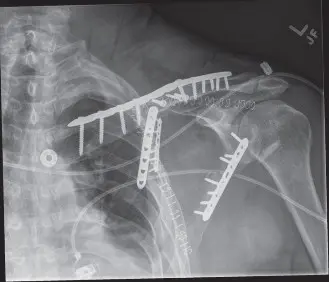

شكل 1: فحص CT قبل الجراحة مع إعادة بناء ثلاثي الأبعاد يوضح كسرًا معقدًا في جسم وعنق لوح الكتف مع إزاحة وزاوية كبيرة. هذا التصوير التفصيلي ضروري للتخطيط الجراحي الدقيق وتحديد النهج الأمثل. -